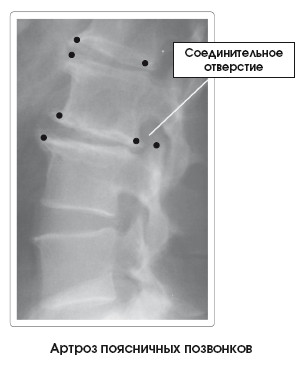

Костные деформации (), называемые остеофитами, шпорами или пиками костей, характеризуют данное заболевание. Они бывают выраженными в той или иной степени в зависимости от уровня прогрессирования артроза. В зависимости от локализации процесса, размера и потери объема диска могут раздражаться и повреждаться структуры мягких тканей, такие как нервы, проходящие через соединительные отверстия, или межпозвоночные диски.